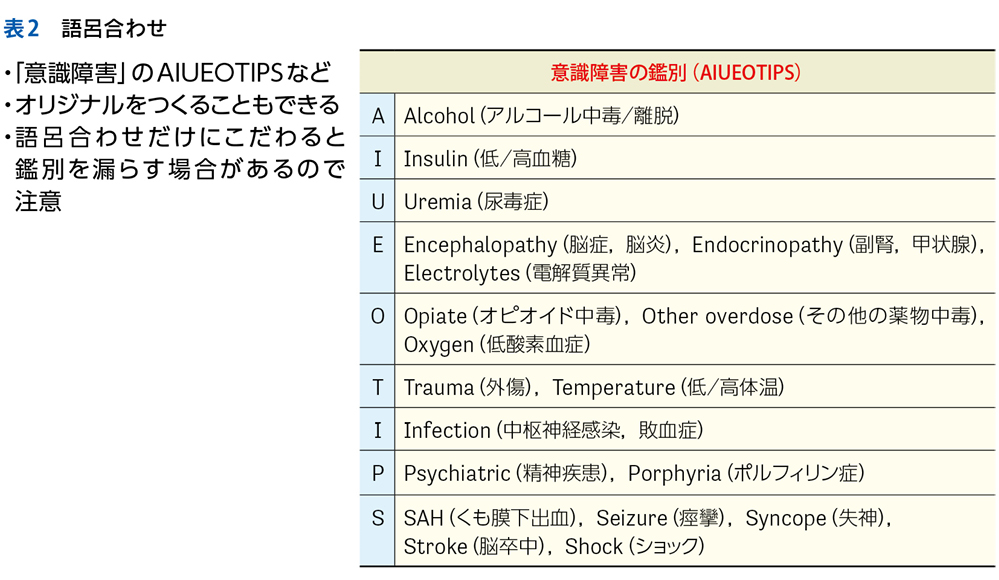

▶ 筆者の提唱する,分析的診断の「型」を図1に示した。冒頭に述べた「オリオン座を分析的に同定する手順」になぞらえ,診断推論を5つのステップにわけている。1つずつ解説しよう。

▶ 表2はNew England Journal of Medicine誌のClinical Problem Solvingに掲載されたケース2)に少し変更を加えてそのプロセスを示したものだが,ここでは「一過性意識消失」という症候からスタートして症候群診断(表中の★)を反復して最終診断に至っている。